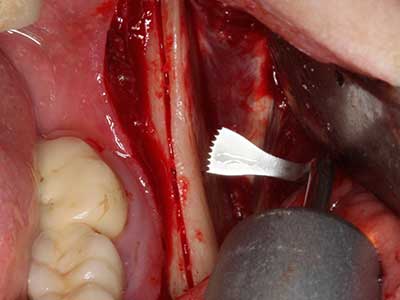

Пиезохирургията има допълнителни предимства при събиране на костни блокове. В допълнение към високата прецизност при остеотомията, описана по-горе, употребата на фините режещи накрайници значително намаляват загубата на материал. Голяма загуба на материал по време на събиране може да се очаква с дебелите накрайници, особено при употреба на борери Линдеман (Lakshmiganthan, Gokulanathan et al. 2012). Базалното разделяне, което е необходимо, особено за присадка на блок при ретромолар, е улеснено от специално създадени правоъгълни триони. В резултат на това, пиезохирургията е разглеждана като прецизна, улеснена и безопасна процедура за събиране на костни блокове в ретромоларното пространство (Happe 2007) (Фиг. 1-12).